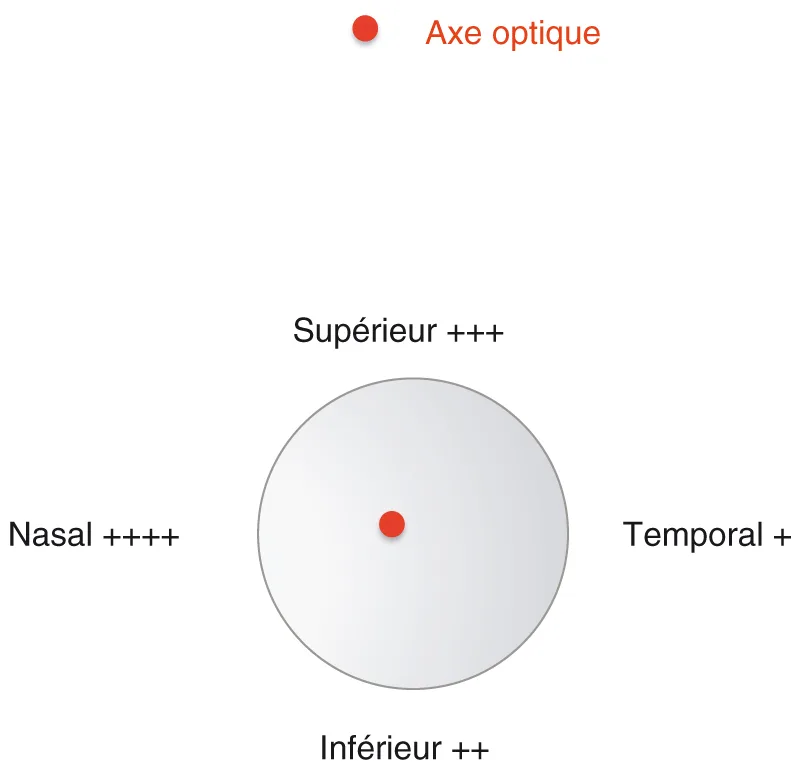

méridien sur lequel est centré l’incision : ainsi le siège temporal, le plus distant de l’axe optique, est le moins astigmatogène, alors que le siège nasal l’est le plus (figure 3.9) ;

Figure 3.9. Caractère astigmatogène de l’incision : minimal en temporal, maximal en nasal.